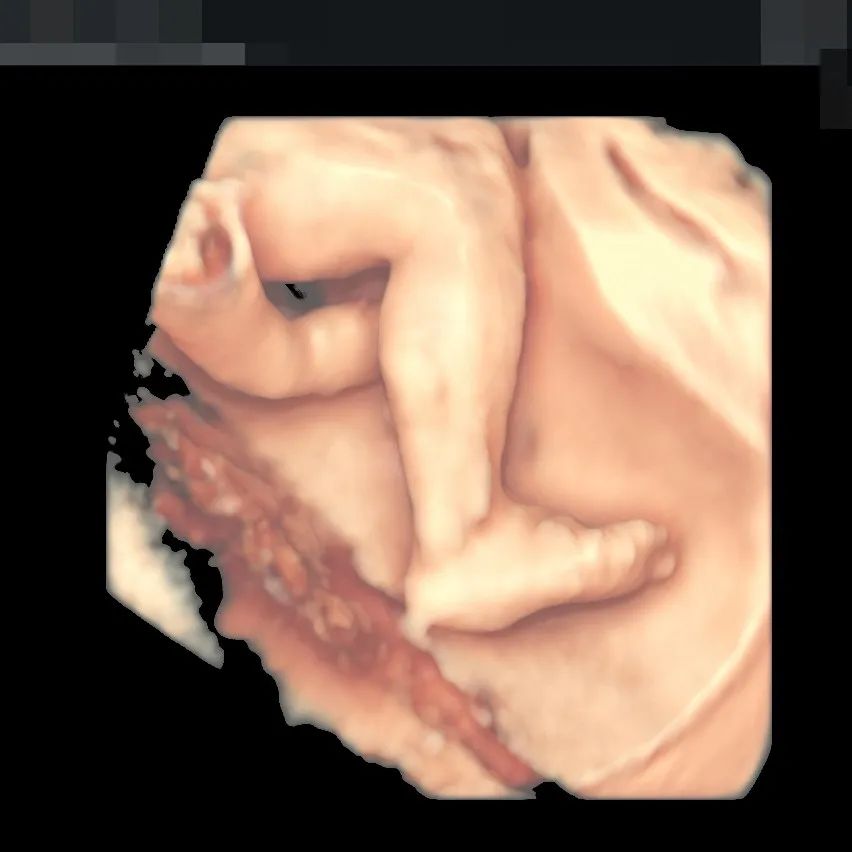

▲190斤孕妈王女士,不仅做了全面筛查,还留下了宝贵的胎儿影像,全家人都非常满意

▲孕妈肚皮脂肪较厚,羊水情况也不好,在和平进行了全面筛查